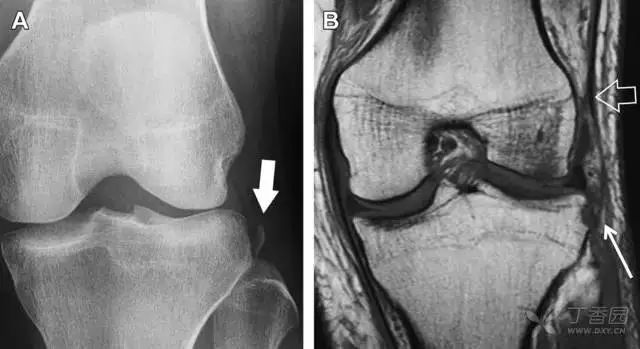

11Segond 骨折

Segond 骨折是发生在胫骨平台外侧的垂直撕脱性骨折(图 4)。这种骨折在前后位 X 线片上显示最佳。

屈曲位时膝关节受到内旋暴力作用,导致皮质骨撕脱性骨折,这种骨折常发生在运动员身上。常引起股骨内髁和胫骨平台后内侧骨挫伤,75%~100% 的患者伴前交叉韧带断裂,33% 的患者伴外侧半月板损伤。

图 4 一位足球运动员的 Segond 骨折

A 正位片示关节线下方胫骨外侧皮质撕脱(箭头)。B MRI 冠状位 T1 加权像示附着于髂胫带的骨折碎片(空箭头)。